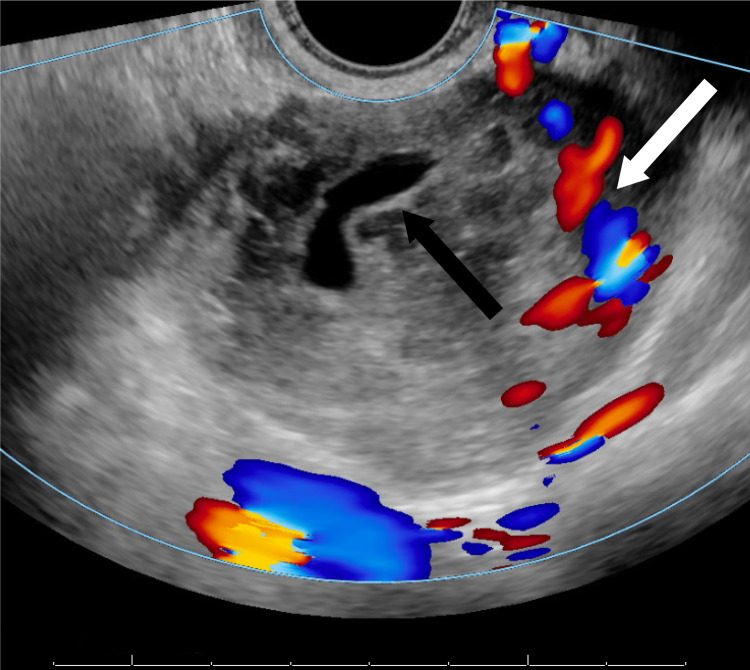

- 자궁 초음파 검사: 자궁 내막, 난소, 난관 상태를 확인하는 영상 검사.

- 경질 초음파 vs 복부 초음파: 임신 준비 시 경질(질식) 초음파가 정확하며, 자궁근종, 낭종, 자궁내막증 등 질환 조기 발견 가능